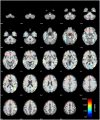

Materials and methods: T1-weighted images from 5,518 women (MAge = 70.20, SD = 3.54; age range: 65-82 years) and 7,595 men (MAge = 70.84, SD = 3.68; age range: 65-82 years) without neurological or psychiatric impairments were included in voxel-based morphometry (VBM) analysis in CAT12 with threshold-free-cluster-enhancement (TFCE) across the whole brain.

Results: We found a significant decrease of GM volume in women in the superior frontal gyri, middle temporal gyri, fusiform gyri, temporal poles, cingulate gyri, precunei, right parahippocampal gyrus and right hippocampus, right ventral diencephalon, and right pre- and postcentral gyrus. Only small effects were found in men in subcallosal area, left basal forebrain and entorhinal area.